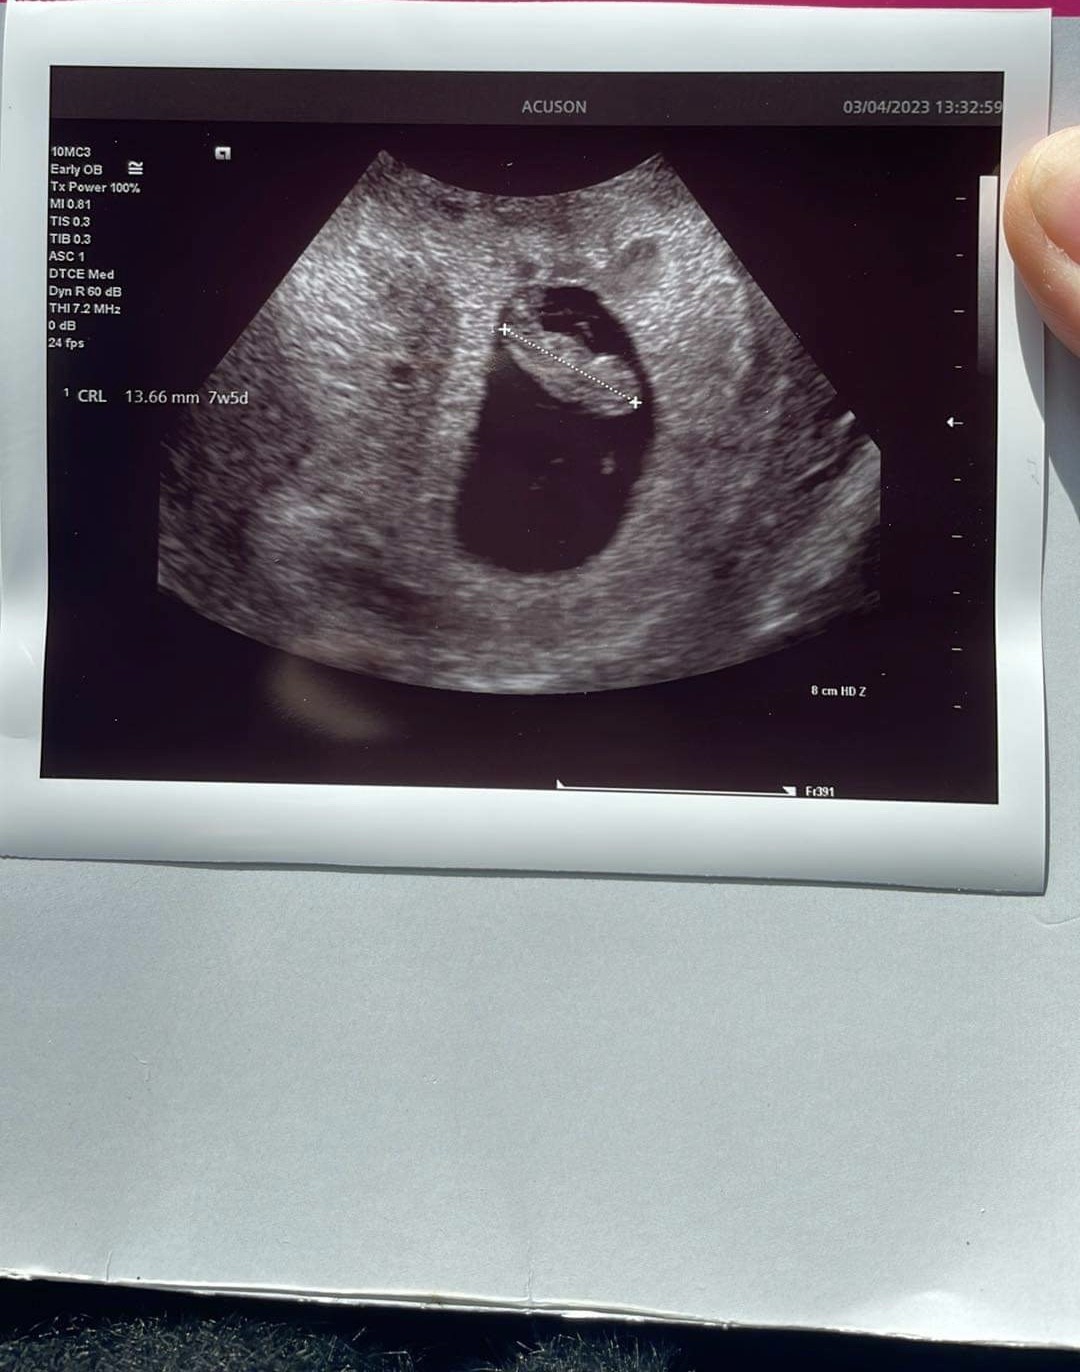

Z Nasza Boróweczką wszystko dobrze, rośnie jak na drożdżach , widać już zalążki rączek i nóżek. Serduszko bije 166 uderzeń na minutę. No i już dorównał do terminu z OM czyli aktualnie jestem 7+6 ❤️

• CDCEC980-92B2-40D2-85E2-1DCC62020893.jpeg

CDCEC980-92B2-40D2-85E2-1DCC62020893.jpeg

223 KB · Wyświetleń: 143